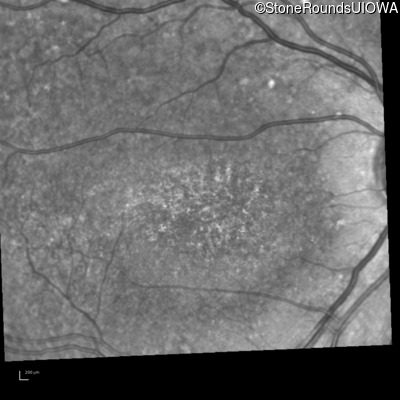

Blue Autofluorescence - Left - 10/125 -1

Exemplar